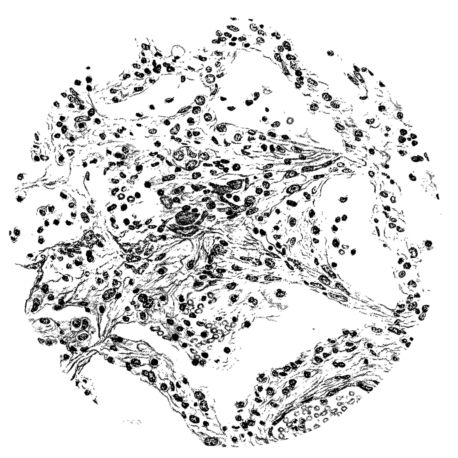

FIG. IV. AUTOPSY NO. 205. CONGESTION AND EDEMA OF THE SUBMUCOSA AND REGENERATION OF THE TRACHEAL EPITHELIUM.

The changes are less marked, perhaps, in the trachea than in its finer ramifications. The mucosa is constantly more or less destroyed and large areas, usually focal, are entirely devoid of their epithelial covering. This is replaced by a sparse exudate, composed largely of red blood cells, mucus, a small amount of fibrin, and nuclear fragments (Fig. II). It may dip into the submucosa for a short distance, but usually these indentures are associated with the ducts of the mucous glands into which the inflammatory reaction extends. A more striking feature than the exudate, however, is the edema and the congestion of the submucosa. The loose areolar tissue of the submucosa is spread widely apart, and throughout it distended blood vessels are very conspicuous. Occasionally such a vessel is broken and actual hemorrhage appears in the submucosa. Occasionally, too, the inflammation extends down the duct to the mucous gland itself, and here, also, aplastic inflammatory reaction is evident, inasmuch as the acini now stain intensely red with the cells undifferentiated from each other and specked here and there by broken remains of the dead nuclei (Fig. III). After the disease has continued for a short period, even at the end of five or six days, some regeneration of the epithelial lining may be seen (3) (Fig. IV). But despite this, the acute picture persists, and there goes on, side by side, an attempted repair characterized by epithelial regeneration and the same evidence of acute change. Since the lesion is essentially a superficial one, scars or contractures of any extent are not encountered in the trachea, even in examples of the disease that have ended fatally only after many weeks.[4]